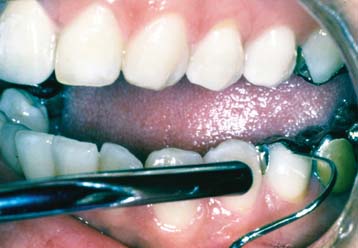

Patients should be instructed in special plaque-control measures, especially around pontics and connectors, and the use of special oral hygiene aids such as floss threaders (Fig. 32-2). If the pontics are properly designed (see Chapter 20), floss can be looped through the embrasure spaces on each side, and the loop can be pulled tightly against the convex pontic tissue surface. A sliding motion is then used to remove dental plaque (Fig. 32-3). Flossing under pontics is essential for improving prosthesis longevity. When dental floss is used, the mucosa beneath pontics remains healthy; without it, mild or moderate inflammation results.1 Tissue response has been shown to be independent of the pontic material.2

Fig. 32-3 The patient should be instructed in the use of floss to clean partial fixed dental prostheses.